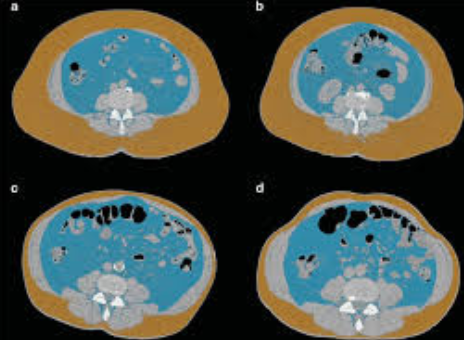

내장지방, 종종 '비스테로이드 지방'으로도 불리는 이 지방은 우리 몸의 내부 기관 주변에 저장된 지방입니다. 이는 피하 지방(피부 바로 아래에 있는 지방)과는 달리, 간, 위, 콩팥 등의 주변에 위치하고 있습니다. 이러한 지방은 단순한 에너지 저장의 역할을 넘어, 호르몬의 분비와 같은 다양한 생리 활동에 중요한 역할을 하는데, 이 글에서는 내장지방 빼는법에 대해 모두 알려드리겠습니다.

내장지방의 증가는 외적으로 확인하기 어려우므로, 정기적인 건강 검진을 통해 체지방률, 내장지방, 콜레스테롤 수치 등을 확인하고 관리하는 것이 중요합니다. 이를 통해 자신의 건강 상태를 정확히 파악하고, 적절한 대응 방안을 마련할 수 있습니다.